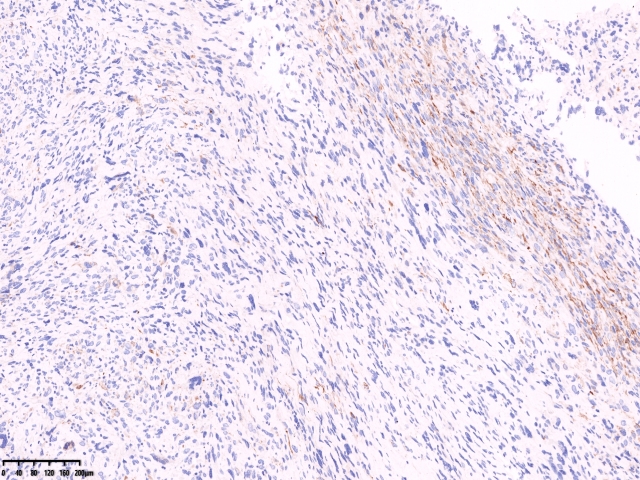

免疫组化

SMA

Caldesm部分+

CD10部分+

CD10

ki67

cd34

ER 部分+

PR-

Desmin-